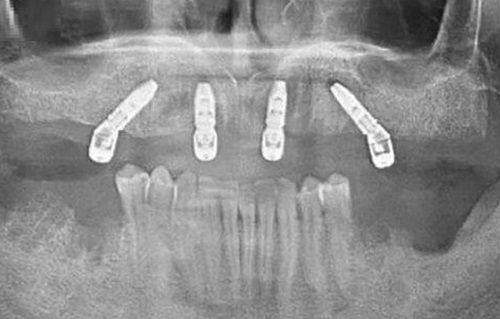

医院配备了精良的口腔诊疗设备,如数字化口腔全景机、口腔CT等。这些设备能够为医生提供正确的诊断依据,帮助医生更精细地制定治疗方案。例如,数字化口腔全景机可以清晰地拍摄口腔全景图像,让医生全方面了解患者口腔的整体情况;口腔CT则能够提供三维立体的口腔影像,对于复杂的口腔疾病诊断具有重要意义。

种植牙项目也是医院的重点项目之一。医院引进了多种有名品牌的种植体,如瑞士ITI种植体、韩国奥齿泰种植体等。不同品牌的种植体价格有所差异,瑞士ITI种植体的质量和稳定性较高,价格相对较贵;韩国奥齿泰种植体性价比高,价格相对较为适中。一般来说,单颗种植牙的价格在几千元到上万元不等,具体价格会根据种植体品牌、患者的牙槽骨情况等因素而定。